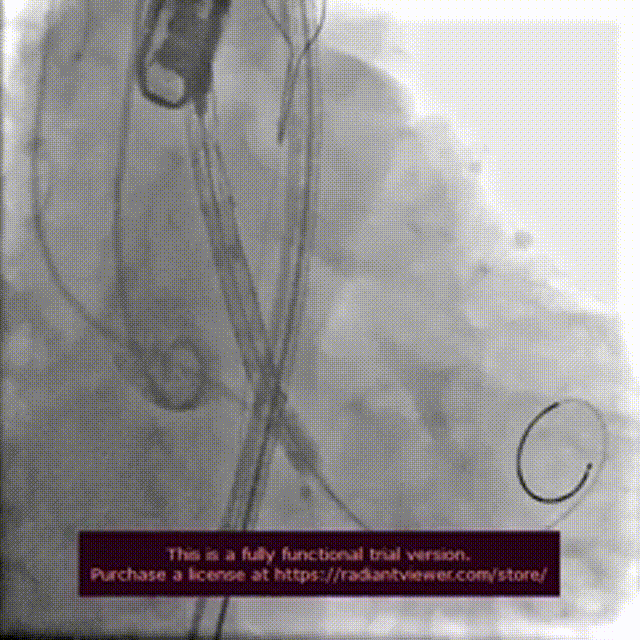

手术过程:

术前造影检查,主动脉瓣大量返流

圈套器辅助下,送入30mmVitaflow瓣膜

造影定位,可见无冠瓣叶较高

快速起搏条件下前期释放2/3瓣膜

造影显示瓣膜位置良好后完全释放

术后造影

数字减影模式检查下肢血管